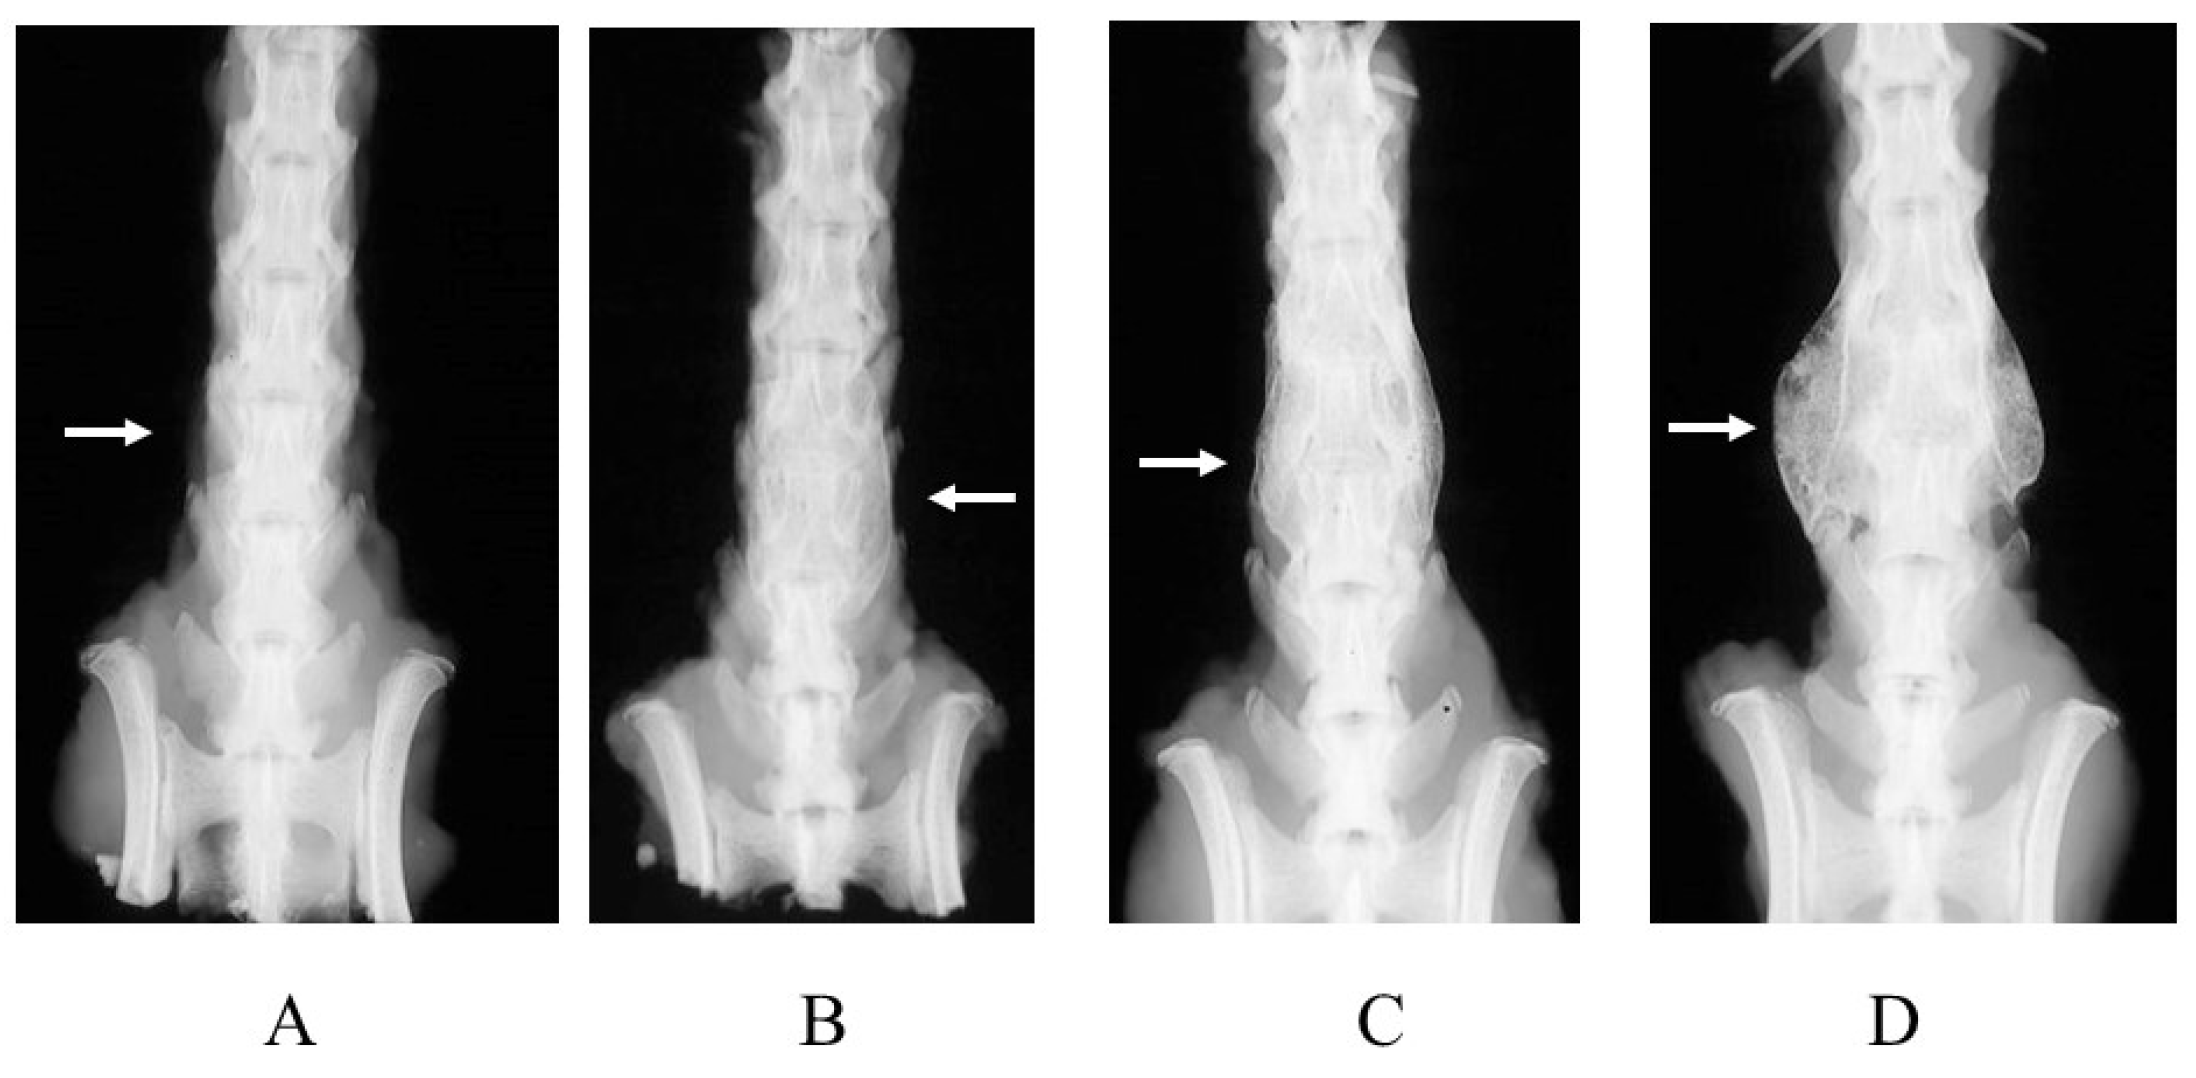

2.2. Radiographic Analysis

| Group | No. Assessed | Fusion Score (Mean ± SD) | |

|---|---|---|---|

| Group I | Carrier alone | 12 | 0.75 ± 1.21 |

| Group II | 3 μg BMP-2 without abaloparatide | 24 | 1.44 ± 1.41 |

| Group III | 3 μg BMP-2 with abaloparatide (3 times/week) | 24 | 3.12 ± 1.08 * (vs. Groups I and II) |

| Group IV | 3 μg BMP-2 with abaloparatide (6 times/week) | 24 | 3.04 ± 0.78 * (vs. Groups I and II) |